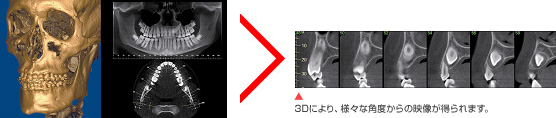

パイナップルが人の前にあるのが分かる影が写りました。CTはこの原理を使用し2DのX線写真で見えなかった病巣やインプラントの埋入方向などを色々な角度から見る事が出来るのです。その画像をもとに診断し患者様に分かりやすくご説明します。

それは2D撮影では写らない情報がCTなら3Dで得られるからです。間違った診断や治療を防ぐために、近年CT撮影による情報がインプラント治療等の診断において必須になっています。